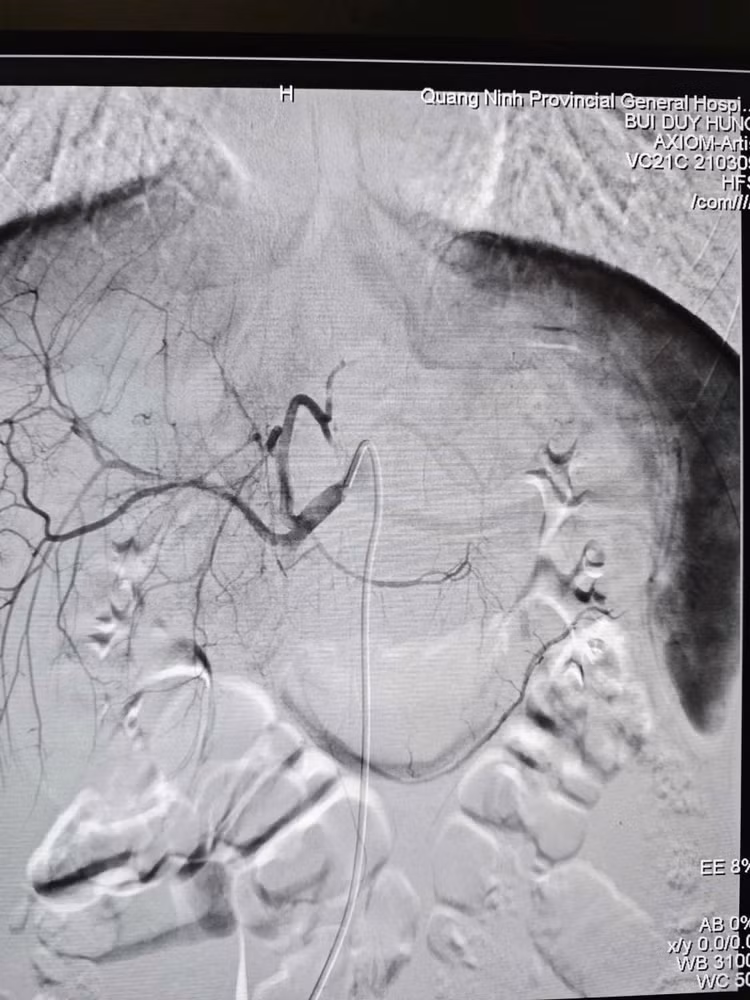

Hình tổn thương trên phim chụp DSA - Ảnh BVCC

Dưới sự hỗ trợ của hệ thống DSA hiện đại, ê-kíp bác sĩ đã luồn ống thông (Microcatheter) siêu nhỏ 1.9F tiếp cận siêu chọn lọc vị trí nhánh động mạch gan đang chảy máu và nút tắc bằng vật liệu chuyên dụng Spongel.

Ê - kíp can thiệp mạch do BSCKII Bùi Duy Hưng - Phó khoa Chẩn đoán hình ảnh – Điện quang can thiệp trực tiếp thực hiện